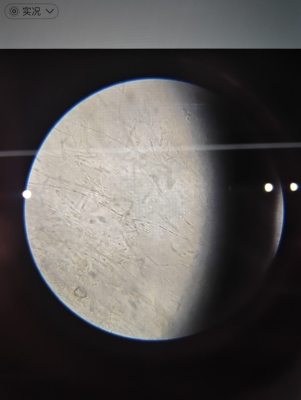

禽波尔纳病毒,热衣原体,疱疹,毛滴虫,巴拉米哥,双病毒荧光pcr检测